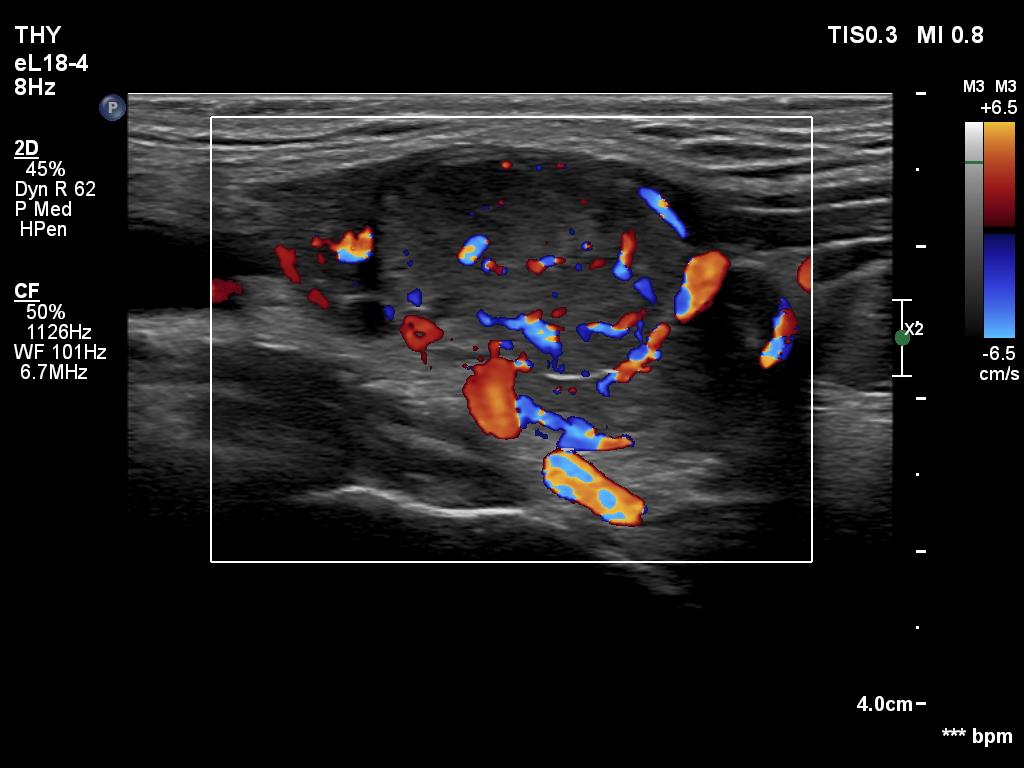

Ultrasonography. The thyroid was hypoechoic. The right lobe had a heterogeneous, dominantly minimally/moderately hypoechoic nodule in the ventrolateral part which had irregular borders and both perinodular and intranodular vascularity. There was another, hyperechoic star-like lesion in the central part of the right lobe. This lesion presented microcalcifications and was avascular. The left lobe was homogeneously hypoechoic.